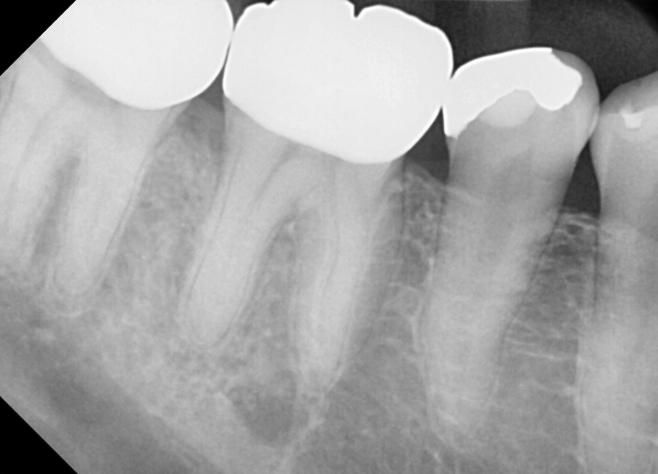

여기서 진단 받은 바로는 해당치아의 바깥족 잇몸에 4~5mm 정도, 설측에 8mm정도 치주낭이 있다고 하십니다.(해당 치아 외에 주변 잇몸은 문제 없음)

8미리 정도의 포켓이면 잇몸수술을 해도 뼈가 차기 어려우며 어차피 뽑게될것이라고 임플란트를 권유하시는데요, 이정도면 발치를 해야할까요? 현재 딥클리닝 하고 3주째 통증이 심해서 계속 진통제를 복용하고 있는데 통증이 줄어들지 않습니다. 한국에서 살릴수 있는 치아라면 최대한 버텨볼려고하고, 어차피 뽑아야한다면 발치라도 해외에서 하고자 합니다.

(또는 한달주기로 몇번 클리닝을 했는데도 점점 아파지는 주기와 통증이 커집니다. 혹시 잇몸 문제가 아니라 치아가 크랙일수도 있으까요?)

치주낭이 8MM라면 잇몸상태가 많이 안좋은거 같긴합니다. 사진상에 보이는정도라면 일단은 잇몸 치료를 하면서 관리를 받아보시는게 좋을것같습니다.

치아에서 특정 부위의 치주낭이 8mm 나오는 경우는 치아 뿌리 부위의 크랙을 의심해볼만합니다 엑스레이상에선 잘 안보일 수도 있습니다